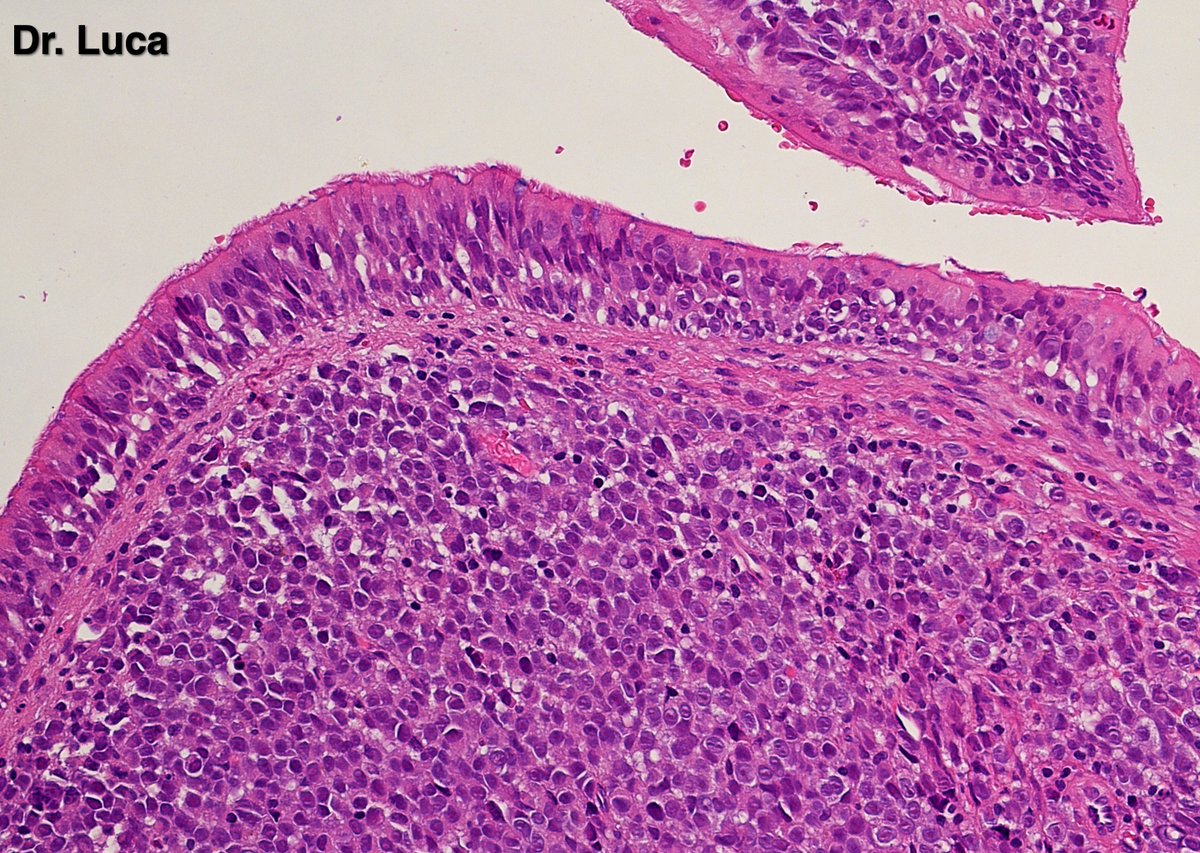

@Pathmath1 @SumantaDas_7 @PoloniaAntonio @ivanaspath @AnapathResident @bansar7 @goziemnweke @Teclis82 @Dr_Brian_Cox @DrBMcGinn @ariella8 @nusrat_xahra @DrRusella_Mirza @glinglerimek @kis_lorand @Venkateshgilly2 @DrBonita16 @DrPayelMondal @DrGeeONE @anjuthevirgo @niki_2389 @pepeheffernan @AngeloCassisa @NeoCrazee @TristanRutland7 Yes, it's a cancer with PNI...I show you the "superficial" layer of this cancer...what is the cancer? and what is the organ? #Pathology #GIpath #PathTwitter #PathResidents #pathboards